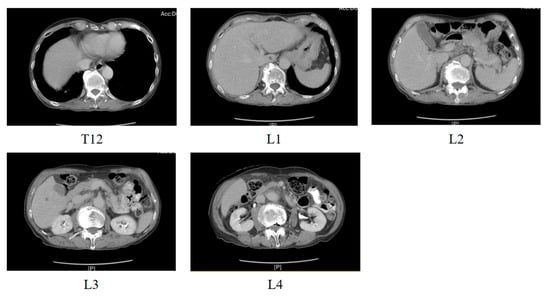

Ordinal Regression Research Based on Dual Loss Function—An Example on Lumbar Vertebra Classification in CT Images

Background/Objectives: Some classification problems involve ordered categories (e.g., low–medium–high), which are better modeled as ordinal regression. This study aimed to propose and evaluate a dual loss framework—Ordinal Residual Dual Loss—for lumbar vertebra classification on CT images to assist L3 identification and sarcopenia [...] Read more.

Background/Objectives: Some classification problems involve ordered categories (e.g., low–medium–high), which are better modeled as ordinal regression. This study aimed to propose and evaluate a dual loss framework—Ordinal Residual Dual Loss—for lumbar vertebra classification on CT images to assist L3 identification and sarcopenia detection. Methods: In this retrospective study, lumbar spine CT images were used to train a deep learning model based on a MobileNet-v3-Large network. The proposed framework combines standard cross-entropy loss for classification with an Ordinal Residual Loss defined on the difference between output probabilities and target ordinal probabilities. Results: Experimental results show that the Ordinal Residual Dual Loss approach outperforms using cross-entropy alone and also surpasses methods from previous studies in lumbar vertebra classification performance. Conclusions: Leveraging a dual loss design that incorporates ordinal information improves vertebral level classification on CT images and has potential to support more accurate automated L3 localization and sarcopenia assessment in clinical practice. Full article